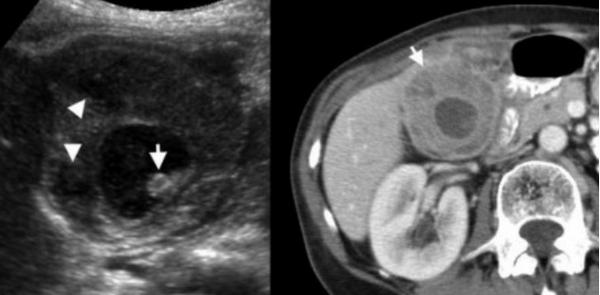

Ксантогранулематозный холецистит.

Ксантогранулематозный холецистит — это воспалительное заболевание, характеризующаяся тем, что в стенке желчного пузыря образуются ксантомы и гранулемы. При исследовании выявляют утолщение стенки желчного пузыря, уменьшение органа в размере, а также интрамуральные узелки, которые визуализируются, как гипоэхогенные включения на УЗИ и гиподенсные на компьютерной томограмме. Данные включения схожи с включениями при карциноме желчного пузыря.

УЗИ и КТ желчного пузыря. Ксантогранулематозный холецистит. Слева на УЗИ визуализируется (помечено стрелками) утолщение стенки желчного пузыря с интрамуральным включением и с камнем в просвете органа. Справа на КТ выявляется утолщение стенки с гиподенсными включениями.

Выше представлено КТ пациента 71 года с ксантогранулематозным холециститом. Постконтрастное КТ. Визуализируется утолщение стенки желчного пузыря с включениями, которые соответствуют абсцессу или фокусам воспаления.

КТ желчного пузыря/Рак желчного пузыря

Наиболее часто встречаемый рак желчного пузыря является карцинома. Карцинома желчного пузыря занимает пятое место по частоте встречаемости среди раков желудочно-кишечного тракта. Чаще его обнаруживают случайно (в 2% случаях) при гистологической проверке после холецистэктомии. Карцинома желчного пузыря выявляется на последних стадиях заболевания так, как себя не проявляет клинически на ранних. Специфических признаков при карциноме желчного пузыря также нет. Рак может поражать желчный пузырь диффузно, целиком стенку или пристеночно. Карцинома желчного пузыря имеет схожую картину с ксантогрануломатозным холециститом, но при постановке диагноза радиологу помогают такие находки:

УЗИ (слева) и КТ (справа) желчного пузыря. На УЗИ ярко выраженное утолщение стенки желчного пузыря (указаны белыми стрелками). Множественные камни в просвете желчного пузыря (указано стрелкой). Компьютерная томография с контрастным усилением. На КТ визуализируются утолщение стенки с внутристеночными гиподенсными включениями. На КТ также выявлено, что процесс распространился на печень (указано стрелкой).